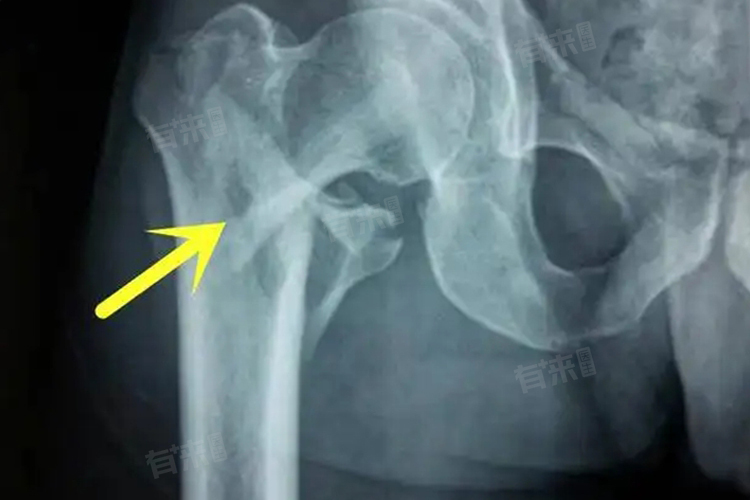

3、诊断:医生通常会根据患者的病史、临床表现以及影像学检查,如X线、CT等确诊。影像学检查能够清晰地显示骨折的部位、形态和程度,为制定治疗方案提供重要依据。